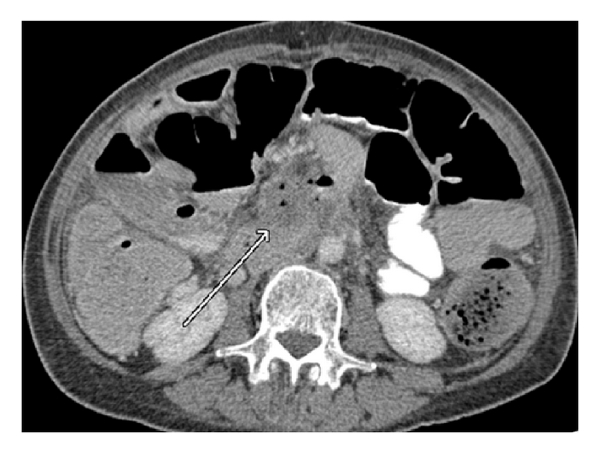

As Figures 1–5 demonstrate, the immediate postablation bed and zone are invariably larger than the original ablated tumor. We remain descriptive because the entire bed was extremely difficult to measure owing to the amorphous, irregular nature of the ablation. Moreover, the ablated tissue is not within an encapsulated organ; therefore, the ablation zone does not have defined borders as seen after, for instance, liver ablation. Four patients that showed continued stable disease are highlighted in Figures 1 through 4. An amorphous, hypoattenuating region with irregular shape persisted in subsequent CT scans in all patients with “stable disease.” Moreover, the ablation zone was typically smaller (due to decreased edema, hyperemia, and granulation tissue) than the immediate postablation bed in the following months and remained stable provided there was no recurrence. Imaging findings demonstrating recurrence are shown in Figure 5. Along with persistent irregular shape the ablation zone showed increased tumor bulk and extension as well as new mass effect (new narrowing of a blood vessel). Enhancement of the ablative bed was variable and often showed increased enhancement in the three-month and longer follow-up images. This was felt to be related to development of granulation tissue and fibrosis.

In our study, we found that the postablation bed is larger in volume than the initial mass. This is expected because it contains the tumor and the ablative margin. The postablation bed and zone appear irregular, amorphous, and hazy without margins or true boundaries. The ablation zone may decrease in size from the initial post-op bed to the initial surveillance study as the surrounding edema/fluid and inflammation resolve revealing the true ablation zone; however, as mentioned above, since there have been reports of an ongoing apoptotic process that persists up to 6–8 weeks after ablation, it will not be unusual to see some increase in volume in surveillance [19, 20]. Therefore, size is considered secondary in the CT evaluation for this reason and because the postablative bed/zone has poorly defined margins, making objective imaging assessment (size, attenuation) cumbersome. This may undoubtedly affect the accuracy and reproducibility of the measurement. Nonetheless, any increase in volume after stabilization of the postablation zone is considered worrisome for recurrence (Figure 5).

Other clues that may suggest recurrence are any new encasement or narrowing of adjacent vessels or any subjective extension of soft tissue outside the boundaries of the previously established baseline ablation zone. However, in patients that have undergone prior radiation therapy or undergo post-IRE radiation therapy, persistent isolated narrowing (without other worrisome findings) is not always recurrence and must be followed with serial imaging, clinical evaluation, and CA19-9 serum tumor markers. Vessels within and adjacent to the ablation bed may show narrowing immediately after the procedure, but this should resolve or at least remain stable in subsequent studies. Often, if narrowing of a vessel is seen with the index tumor it will often persist after ablation. For equivocal cases, PET/CT may play a role in differentiating postablative changes from recurrence [25].